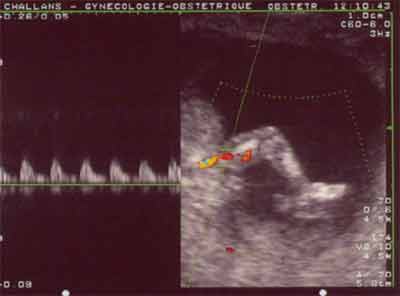

Membres inférieurs : Vaisseaux